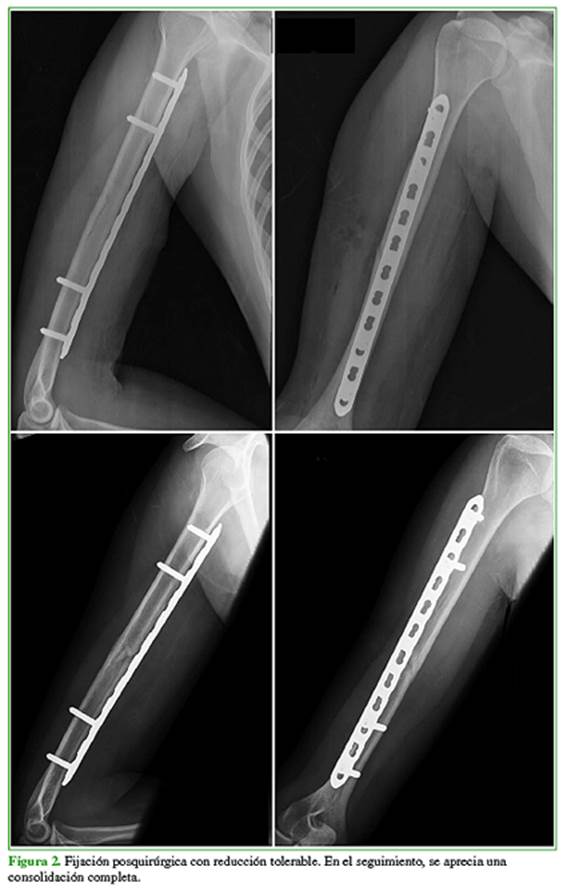

Se utilizaron placas de compresión dinámica de 4,5 mm estrechas, de 12 a 14 orificios. La placa se colocó en la superficie anterior del húmero (Figura 2).